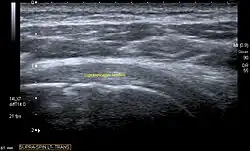

Ultrasound

There are several advantages of ultrasound. It is relatively cheap, does not emit any radiation, is accessible, is capable of visualizing tissue function in real time, and allows the performance of provocative maneuvers in order to replicate the patient’s pain.[28] Those benefits have helped ultrasound become a common initial choice for assessing tendons and soft tissues. Limitations include, for example, the high degree of operator dependence and the inability to define pathologies in bones. One also has to have an extensive anatomical knowledge of the examined region and keep an open mind to normal variations and artifacts created during the scan.[29]

After the introduction of high-frequency transducers in the mid-1980s, ultrasound has become a conventional tool for taking accurate and precise images of the shoulder to support diagnosis.[31][32][33][34][35]

Adequate for the examination are high-resolution, high-frequency transducers with a transmission frequency of 5, 7.5, and 10 MHz. To improve the focus on structures close to the skin an additional "water start-up length" is advisable. During the examination the patient is asked to be seated, the affected arm is then adducted and the elbow is bent to 90 degrees. Slow and cautious passive lateral and/or medial rotations have the effect of being able to visualize different sections of the shoulder. In order to also demonstrate those parts which are hidden under the acromion in the neutral position, a maximum medial rotation with hyperextension behind the back is required.[36]